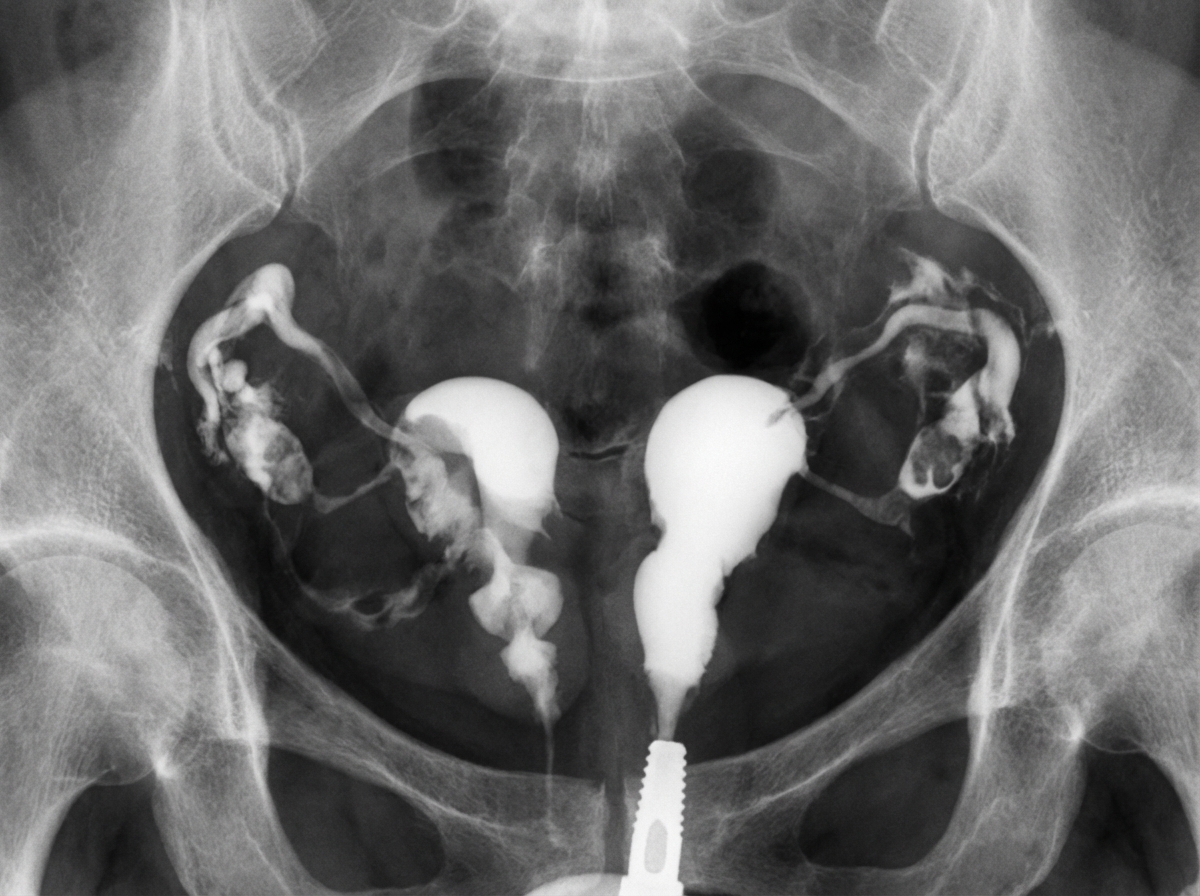

The provided Hysterosalpingogram image demonstrates which of the following uterine anomalies?

Explanation: ***Uterine didelphys*** - Shows **two completely separate uterine cavities** with **no communication** between them on HSG, representing complete failure of Müllerian duct fusion. - Associated with **duplicate cervices** and often **longitudinal vaginal septum**, making it the most severe form of **uterine duplication anomaly**. *Septate uterus* - HSG would show a **single external uterine contour** with **internal division** by a septum, not two separate cavities. - The **fundal contour remains normal** externally, distinguishing it from bicornuate or didelphys variants. *Bicornuate uterus* - Demonstrates **two uterine horns** that **communicate at the cervix** with a **heart-shaped external fundal contour**. - HSG shows **partial separation** of cavities that **converge toward the cervix**, unlike the complete separation in didelphys. *Arcuate uterus* - Shows only a **mild indentation** of the **fundal contour** with minimal impact on the uterine cavity shape. - HSG reveals a **near-normal cavity** with slight **fundal flattening**, representing the mildest Müllerian anomaly.